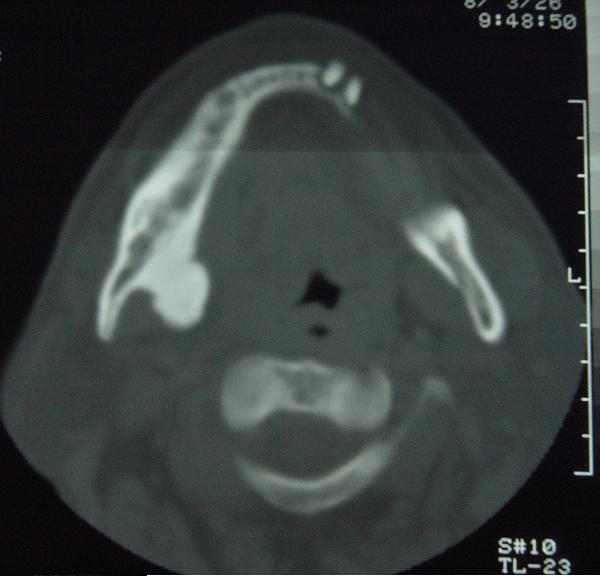

标题: CT12465:下颌骨肿瘤,请会诊 [打印本页]

标题: CT12465:下颌骨肿瘤,请会诊

发现下颌骨肿瘤近30年.逐渐增大.

考虑右侧下颌骨水平部及升部骨纤维异常增殖症可能性大。

考虑右侧下颌骨骨化性纤维瘤。